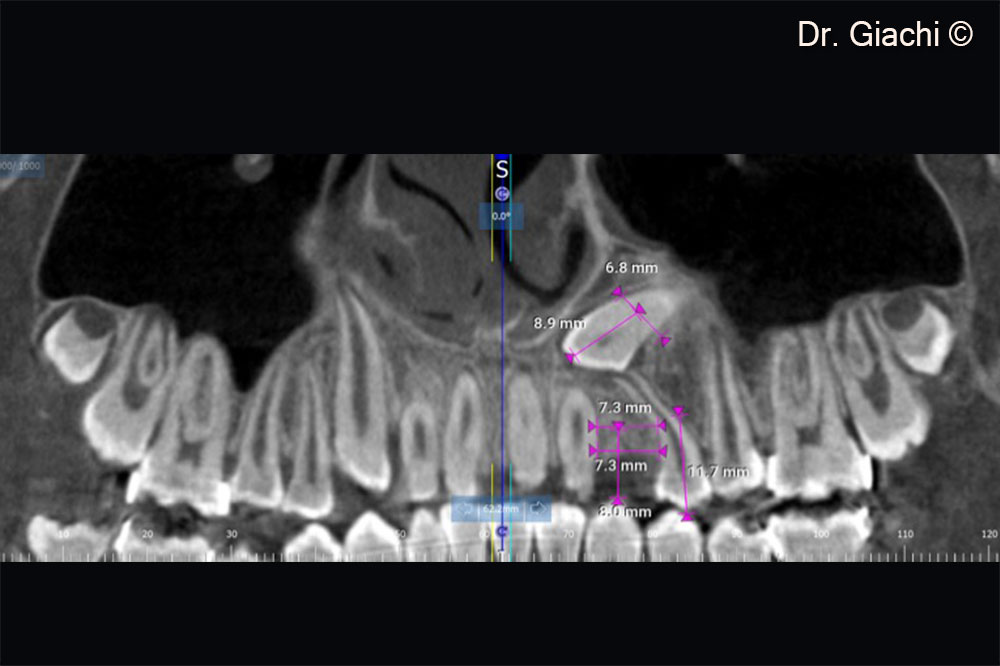

Một bệnh nhân nam (16 tuổi) có răng nanh trên không thể phục hồi bằng phương pháp chỉnh nha truyền thống.